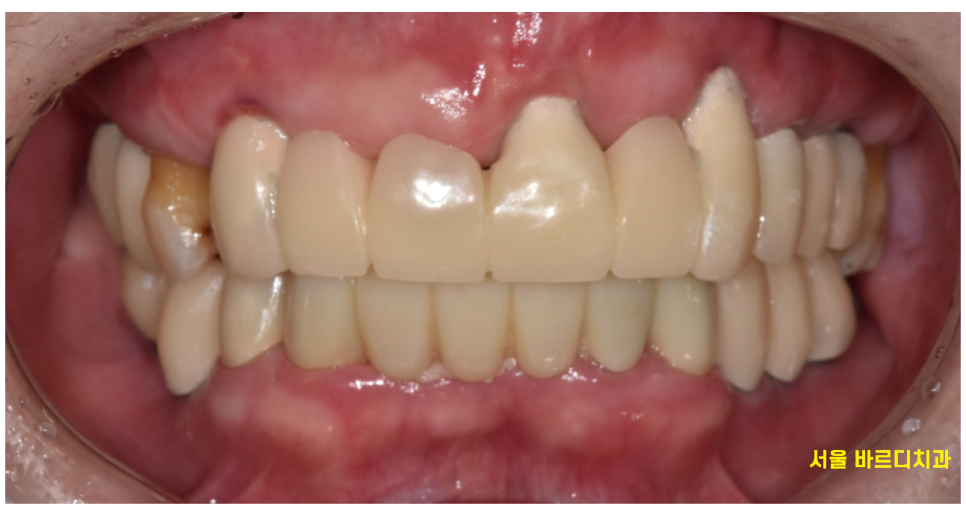

24.04.30

6개월 정도 지나

강동구 임플란트 치료 끝내드렸습니다.

완성 후 씹는게 낯설다고

하셨던 환자분 말씀이 기억이 납니다.

씹는 즐거움을 잊어버릴만큼

오랫동안 어금니 상실을 겪으셨다는 건데요.

어렵게 되찾으신만큼

유지 잘하시라고

임플란트 관리법을 교육해드리면서

치료를 마무리해드렸습니다.